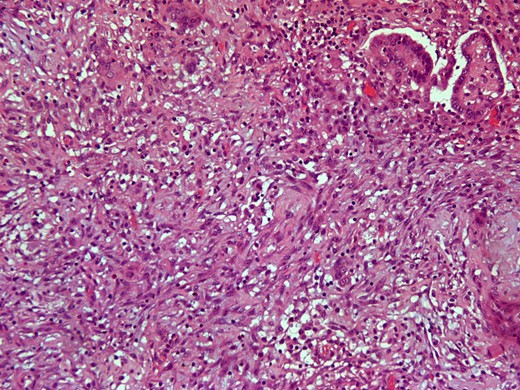

Here we report on a 32-year-old patient who presented at the Emergency Department complaining of acute abdominal pain accompanied by vomiting and diarrhea that had started three hours before. The patient was a para 2 and the latter delivery had occurred nine months before. She had been breastfeeding until 20 days before her ED visit and her menses had not yet resumed. Her medical history was unsignificant and she reported a laparoscopic ovarian cystectomy five years before, of which the histology report was not retrieved. She also had an ultrasound six months before, which described a pelvic multilocular cystic lesion of 11.4 × 8,6 × 12.3 centimeters, which remained untreated. The patient underwent an IV contrast—enhanced abdominal CT which demonstrated sizeable multilocular bilateral ovarian cystic lesions, of 18 cm and 15 cm in dimensions (in the right and left ovary respectively). (Figs 1 and 2). Her tumor markers were as follows (normal values are in parentheses): CA 15.3 = 20.53 U/ml (<25 U/ml), AFP = 1.08 ng/ml (<7 ng/ml), CEA = 0.63 ng/ml (<3.8 ng/ml), CA 125 = 110.40 U/ml (<35 U/ml), CA 19.9 = 50.06 (<34 U/ml), CA 72.4 = 6.74 (<6.9 U/ml). After the completion of preoperative investigations, the patient underwent and exploratory laparotomy. Frozen section revealed bilateral serous borderline tumors, therefore the patient underwent a total abdominal hysterectomy/bilateral salpingoophorectomy and epiplectomy. During surgical procedure astonishing remarks was the necrotized torsion of ovarian masses mimicking infiltrated ovarian neoplasm. (Figs 3–5). The final histology report confirmed the diagnosis of bilateral serous borderline tumors/atypical serous proliferative tumors, staged as pT1cNxMx or FIGO Ic. (Figs 6 and 7). Peritoneal fluid cytology showed mesothelial reactive lesions. The patient’s postoperative course was uneventful. The Multidisciplinary Team Meeting decided on adjuvant chemotherapy (four cycles of CarboTaxol; paclitaxel and carboplatin). Nine months after surgery, the patient remains alive and disease – free.

Intersection where the extrusion component is shown (H&E × 20).

Intersection of demoplastic non-invasive autoimplantation / auto implant. (H&E × 200).